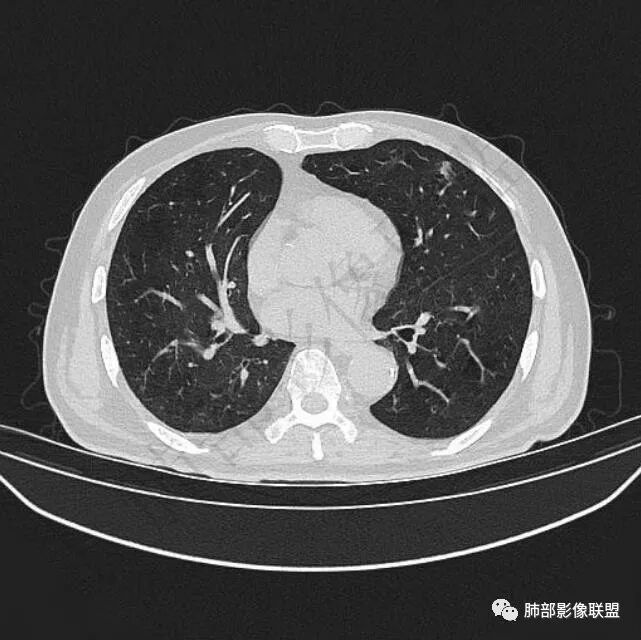

9个月后病灶明显增大,边缘较平直,部分膨隆,锁扣样外观,仍旧缺乏典型深分叶及张力,未见胸膜凹陷。